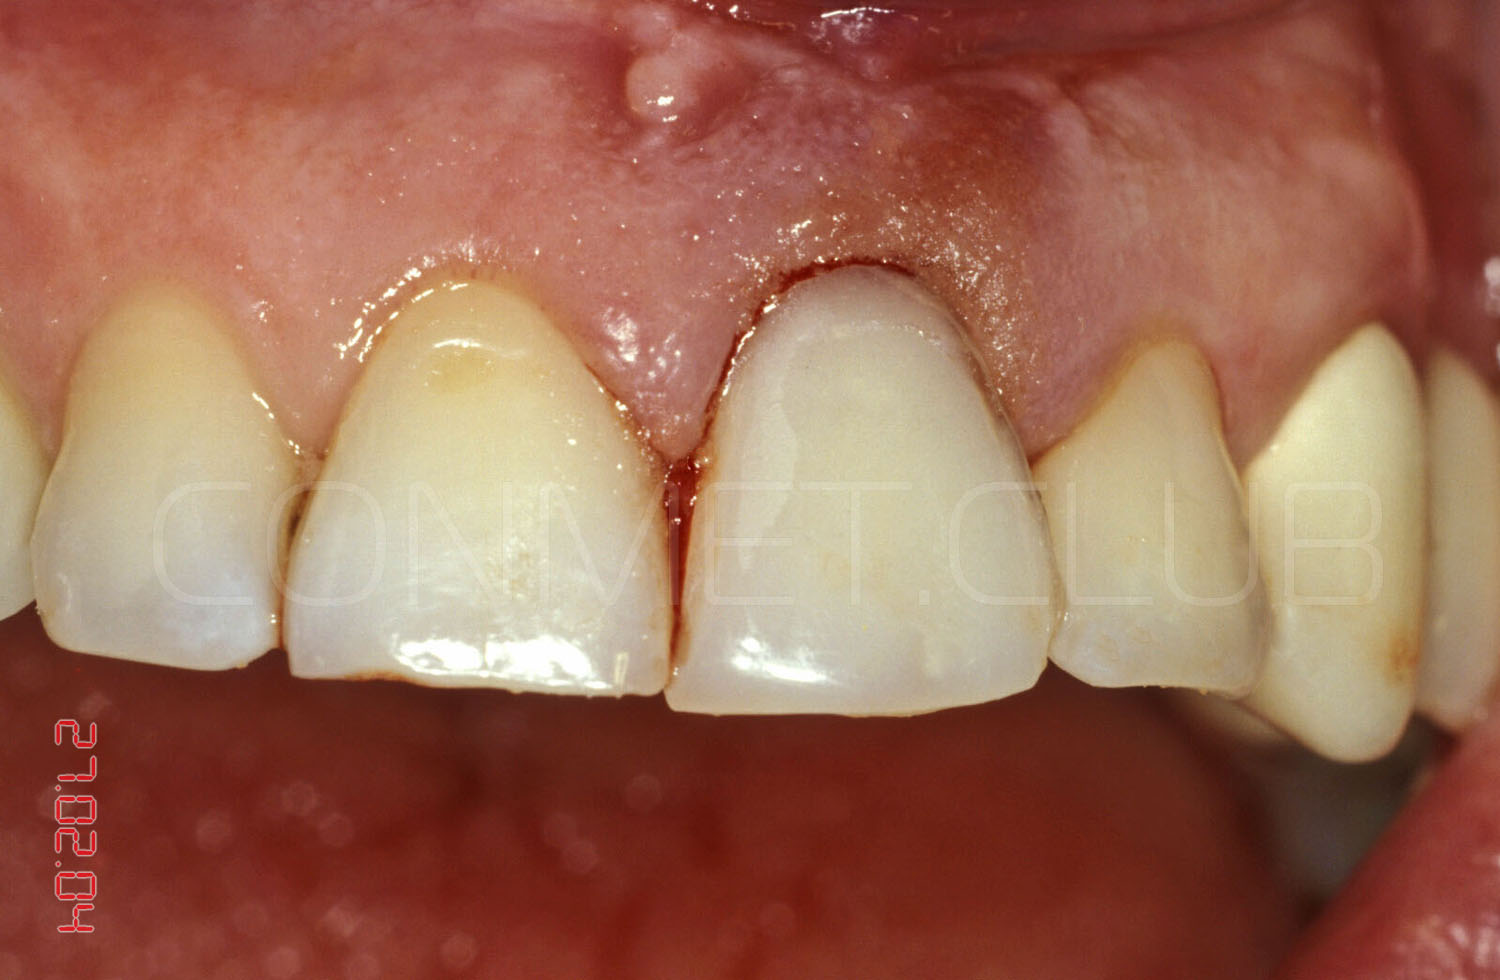

Вид на корень и трещины за три дня до экстракции и немедленной имплантации.

Операция немедленной имплантации была произведена 27.02.2004 года непосредственно после экстракции зуба 21 из-за невозможности дальнейшего лечения данного зуба (две вертикальные трещины корня).